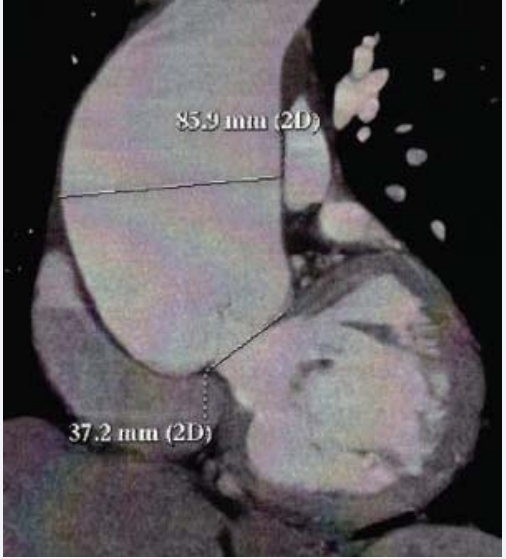

Subsequently, the patient had a CTA (with 3D reconstruction) that confirmed the large ascending aortic aneurysm with 8.6 cm (Figures 4a, 4b and 4c).

Computed Tomography Angiography with measurement of  the diameter of the aneurysm and aortic ring.

Figure 4c: Computed Tomography Angiography with measurement of the diameter of the aneurysm and aortic ring.

Additionally, it is important to underline that the calcium score was zero, there were no identifiable coronary lesions and there were no other aneurysms identified.